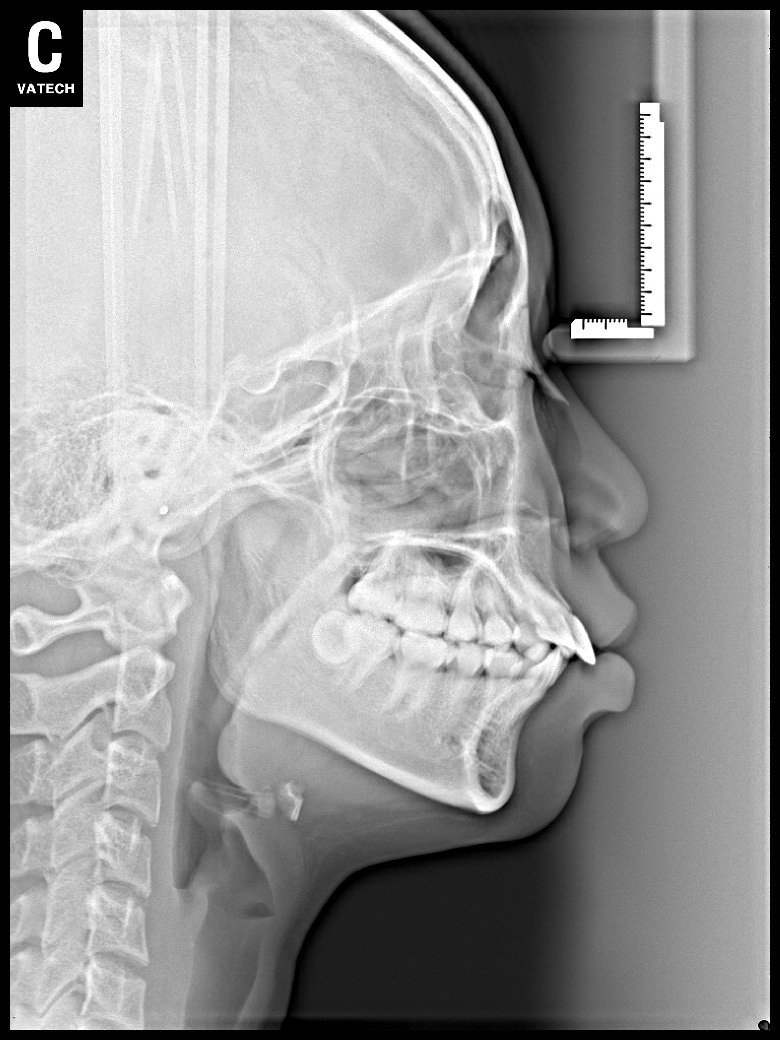

치료 후 사진입니다.